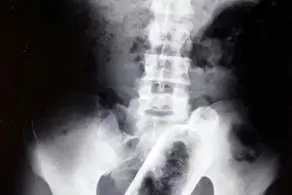

علائم او شامل سر درد شدید، کم بینایی، فلج شدن صورت یا حتی مشکل هنگام خنده بود. پزشکان مشکلات را بررسی کردند و با انجام آزمایش ام آر آی متوجه شدند که دقیقاً در وسط مغز او، کپک ها در حال رشد هستند.